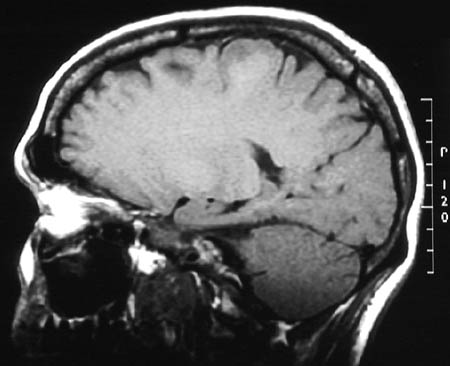

These enhanced MRI scans in sagittal view reveal the presence of a small, ill-defined mass in the superior left frontal lobe. This is an

oligodendroglioma

.